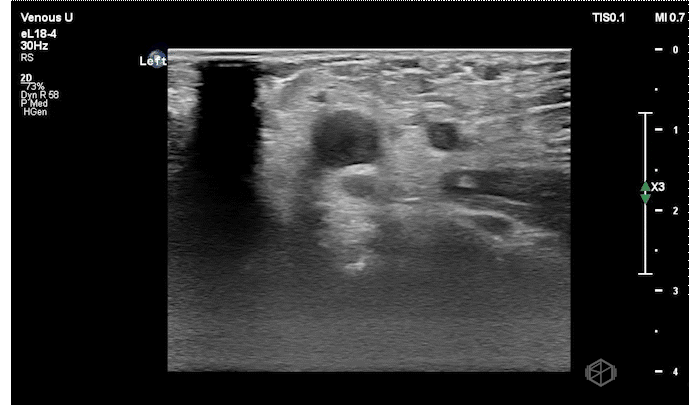

Dr. Vazquez had a 78-year-old female with a history of a recent pacemaker placement present to the ED for shortness of breath and left arm pain. The patient had a new pericardial effusion (which was the real reason for her shortness of breath) as well as the below finding in her LEFT upper extremity.

The patient has an echogenic thrombus visible in the LEFT distal subclavian vein to the branch point at the anterior cubital fossa.

Diagnosis: Left upper extremity DVT